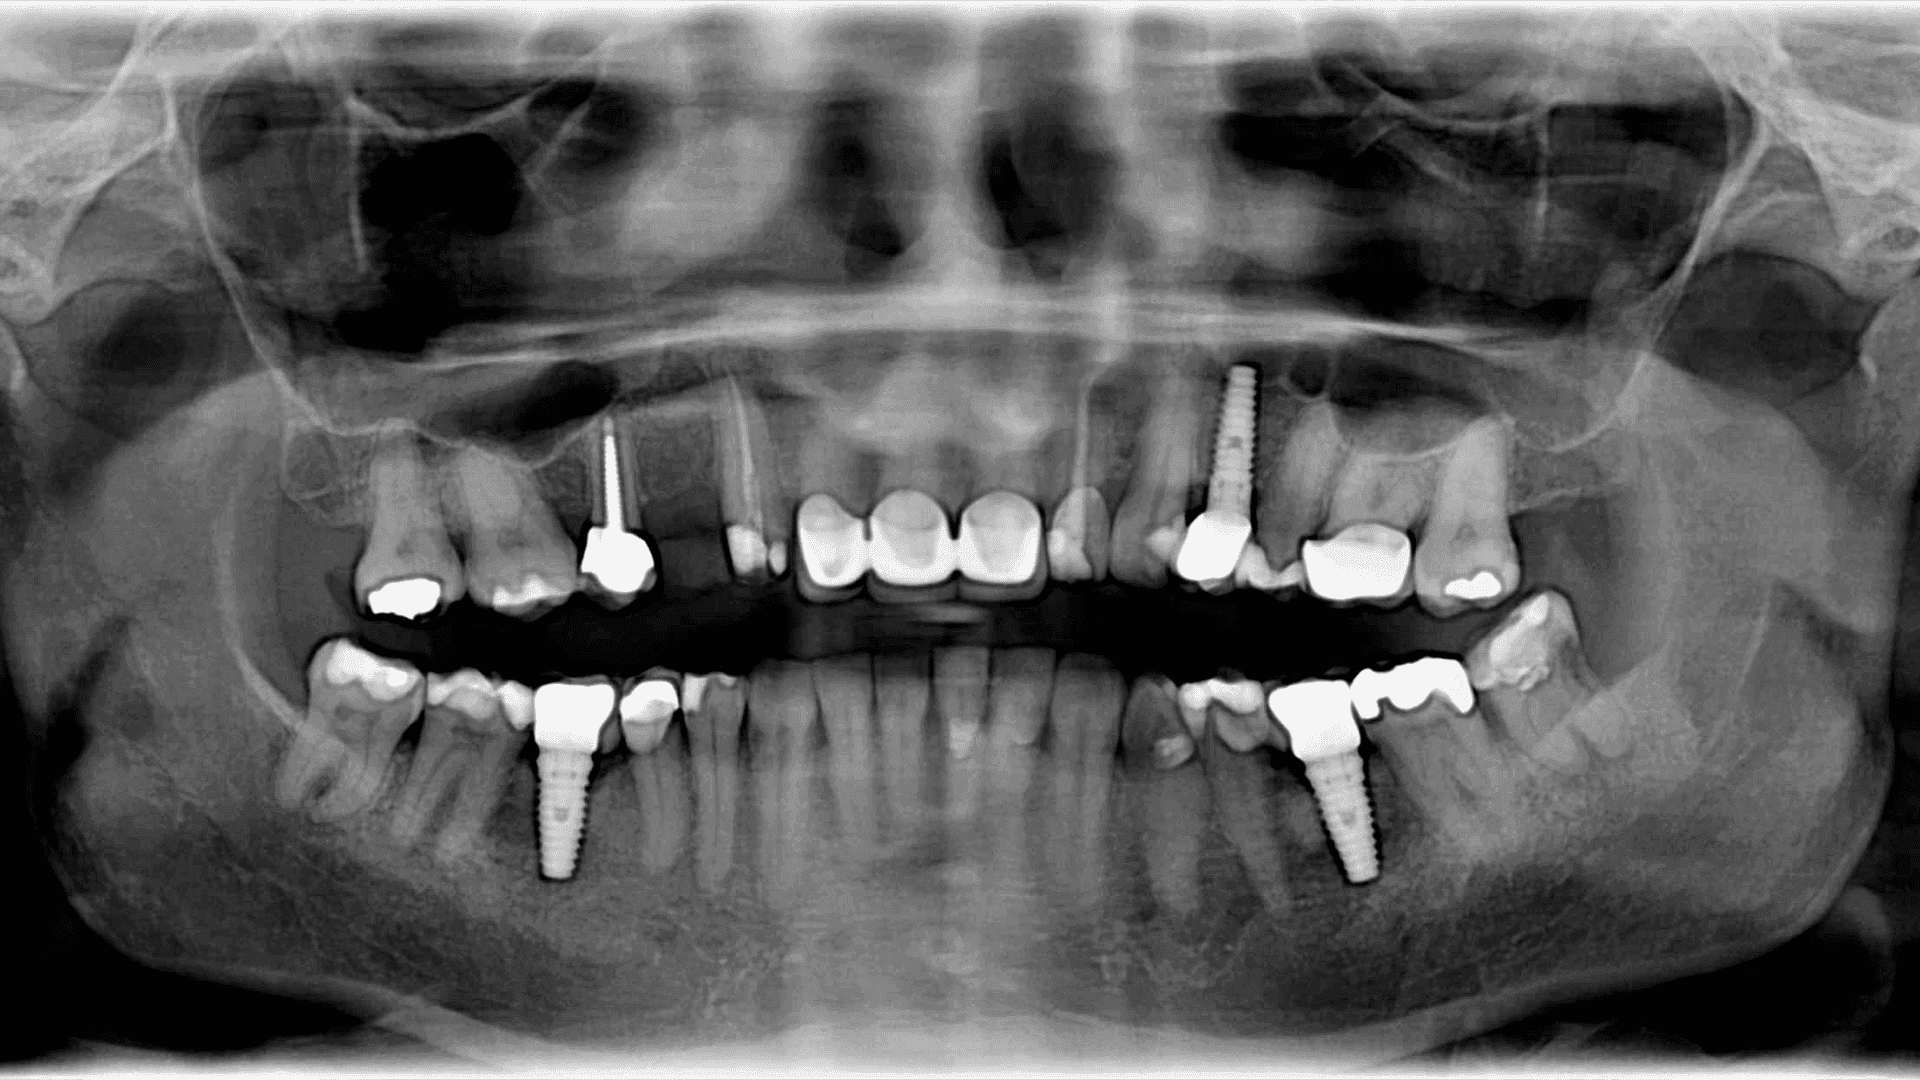

Zdjęcie panoramiczne OPG (Ortopantomogram) to nieinwazyjna metoda diagnostyczna, która dostarcza kompleksowy obraz stanu zdrowia jamy ustnej pacjenta. Technika ta umożliwia uzyskanie jednego dużego obrazu obejmującego zęby, żuchwę, szczękę oraz przyległe struktury kostne. Dzięki temu, OPG znajduje zastosowanie nie tylko w diagnozowaniu problemów z zębami, ale również w ocenie stanu zatok, stawów skroniowo-żuchwowych oraz wykrywaniu zmian patologicznych. Zdjęcia panoramiczne są często stosowane przed rozpoczęciem kompleksowego leczenia ortodontycznego, implantologicznego czy chirurgicznego w obrębie jamy ustnej.

Technologia za zdjęciem panoramicznym OPG opiera się na specjalnym aparacie radiologicznym, który obraca się wokół głowy pacjenta, wykonując zdjęcie łukowe. Dzięki temu możliwe jest uzyskanie pełnego obrazu struktur jamy ustnej na jednym zdjęciu. Zaawansowane systemy cyfrowe przetwarzają te dane, tworząc obraz wysokiej jakości, który może być następnie dokładnie analizowany przez specjalistów. Cyfryzacja procesu diagnostycznego pozwala również na łatwe przechowywanie i udostępnianie obrazów, co jest szczególnie przydatne w przypadku konsultacji interdyscyplinarnych.